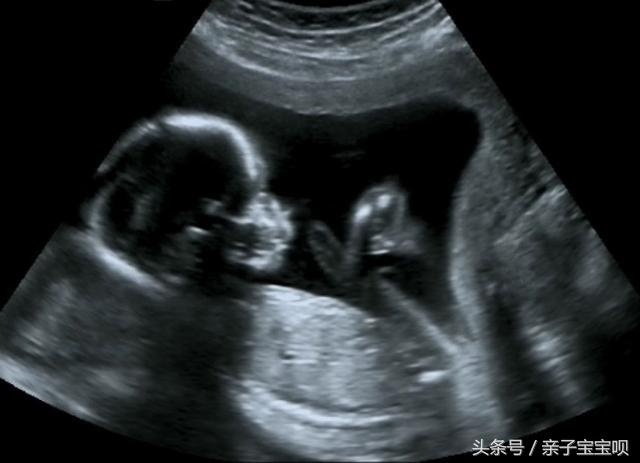

哪知道就在娜娜怀孕八个月的时候突然早产了,吓得老公急忙把娜娜送去医院,到了医院后,发现胎儿横位很是危险,需要立刻手术。

哪知道婆婆拦着不让去,因为是个女孩,婆婆怎么都不愿意生下来,于是就在医院的走廊里面母子二人争吵起来。随着娜娜呼吸声越来越弱,周围的医生也是十分的着急,这时候医生检查发现胎儿的一只手都伸出来了,似乎在抢救,吓得医生赶紧让老公拉开婆婆,准备手术。